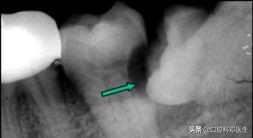

危害二:蛀牙

蛀牙

向前倾斜的阻生智齿,会与邻牙形成一个三角形的间隙,这个间隙易积存食物,而平时刷牙又不能及时完全清除,久而久之就会导致智齿本身以及邻牙(下第二磨牙)龋坏。这种龋坏位置比较隐蔽,不易早期发现,一旦发生疼痛(急性牙髓炎),牙冠常已被严重破坏。即使进行根管治疗,也难长久保存。